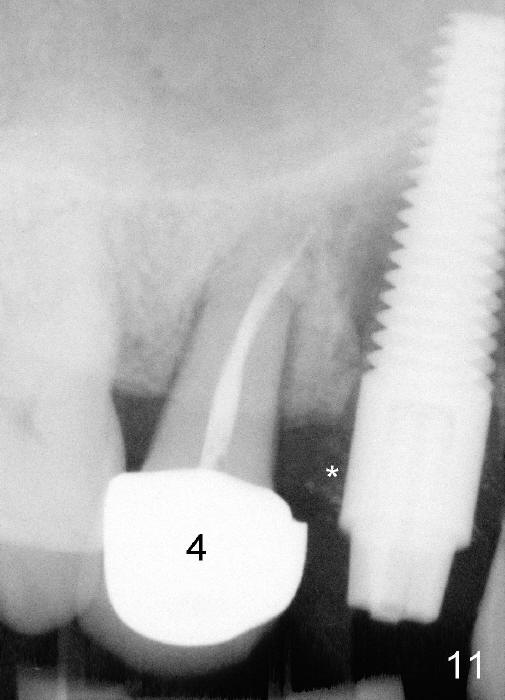

Eighteen days postop, the patient returns for #4 root canal therapy; PA shows bone graft next to the implant (Fig.11 *). Twenty-two days postop, the immediate provisional is dislodged with loss of bone graft over the middle of the buccal surface of the implant (Fig.12 *). The implant and abutment are prepared so that the margin is advanced apically (Fig.13 ^) with accentuation of the retention grooves (*). The provisional is relined and recemented.